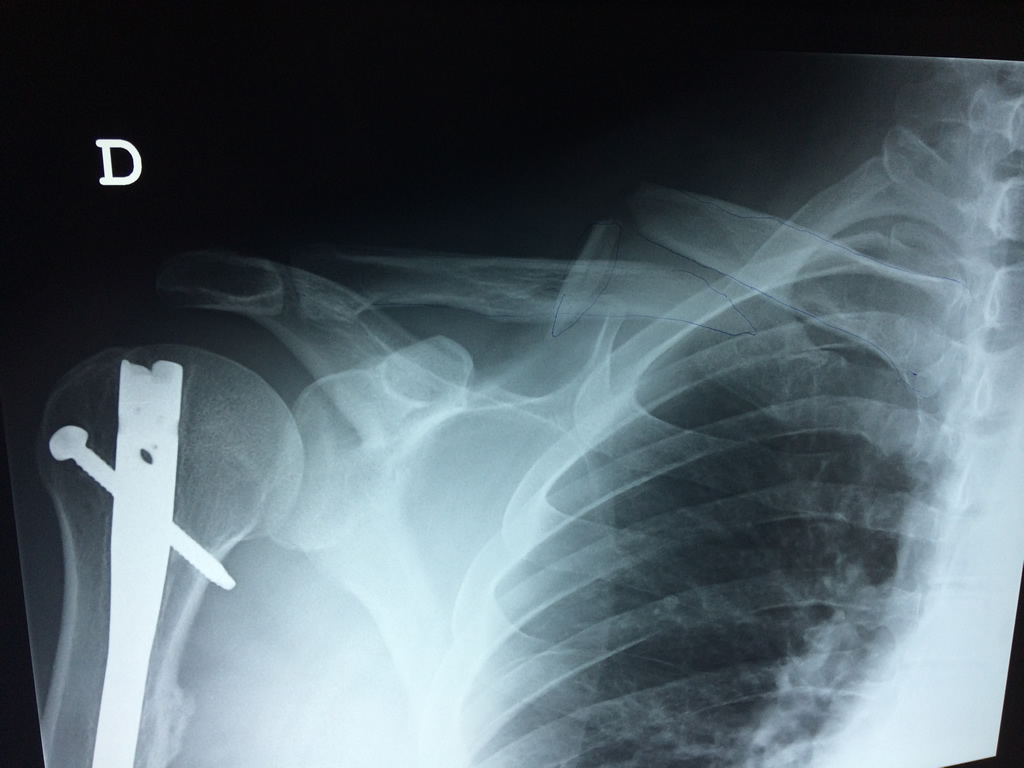

Clavícula

La clavícula es un hueso largo, con forma de "S" itálica, situado en la parte anterosuperior del tórax. Junto con la escápula forman la cintura escapular. Se puede palpar por toda su longitud y se extiende del esternón al acromion de la escápula, siguiendo una dirección oblicua lateral y posterior.

Se considera el único medio de unión entre el miembro superior y el tórax. A pesar de su aspecto, similar al de un hueso largo, posee una estructura semejante a la de un hueso plano, ya que carece de epífisis y de diáfisis, lo que la harían entrar dentro de la clasificación de hueso largo. Carece de un canal medular propiamente dicho.